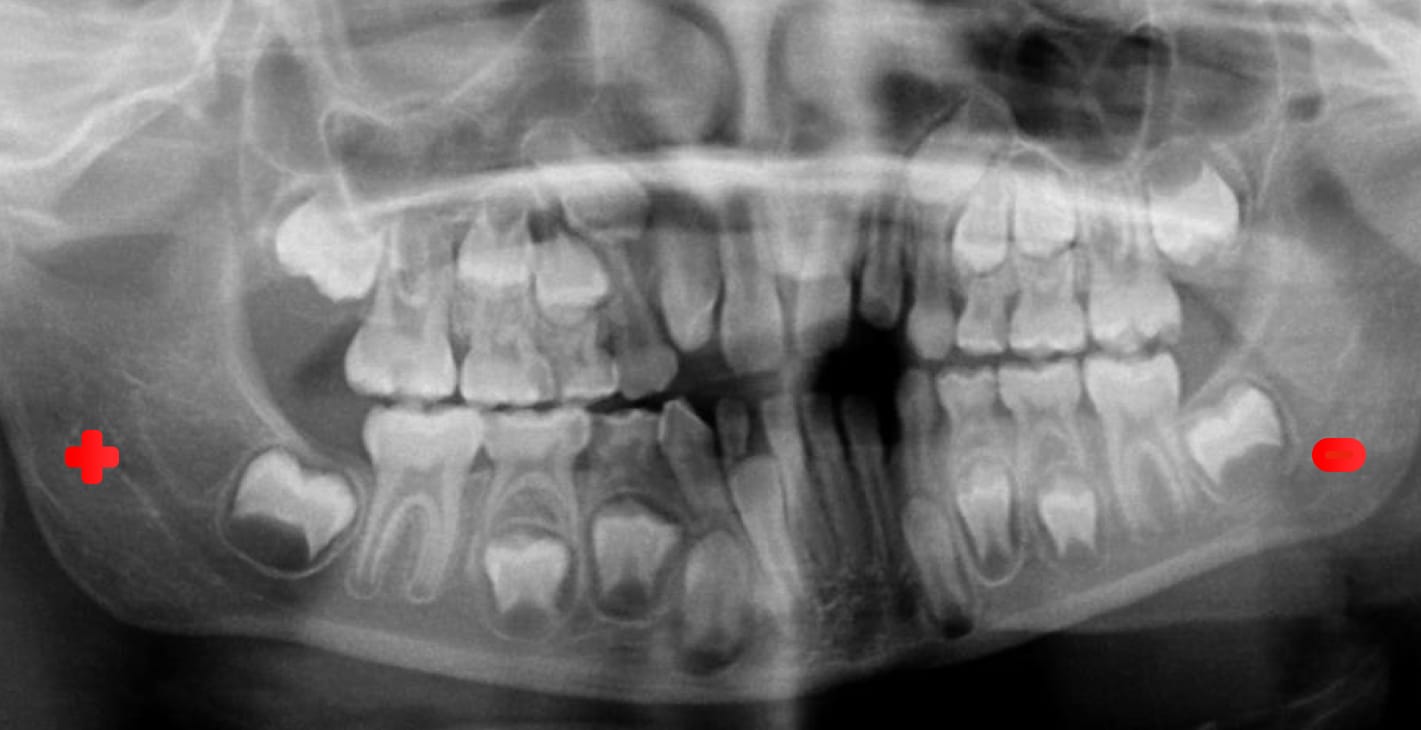

Ortopantomografía (OPG) o radiografía panorámica ¿Qué errores evitar para obtener una imagen que contribuya al diagnóstico preciso? -